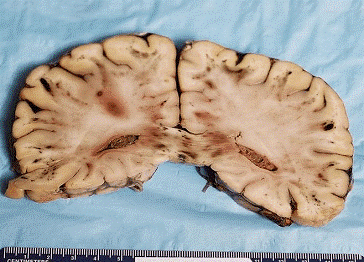

General autopsy revealed diffuse alveolar damage, attributed to viral infection. There was bronchiectasis, emphysema, cardiomegaly and acute tubular necrosis. The fixed brain weight was 1,200 gm. External examination showed scattered small foci of subarachnoid hemorrhage. On sectioning, the cerebral hemispheres and cerebellum showed numerous foci of fresh hemorrhage, almost exclusively in the white matter, ranging from punctuate ones, up to 4 cm in maximum dimension. Submitted: One H&E-stained slide and one unstained slide.

The gross appearance of the brain appears below:

Large and small hemorrhages were present in the white matter and at the grey-white junction, and in the corpus callosum. One hemorrhage was seen in the basal ganglia, the only one in the grey matter. The cerebellum, brainstem and spinal cord also showed small hemorrhages.